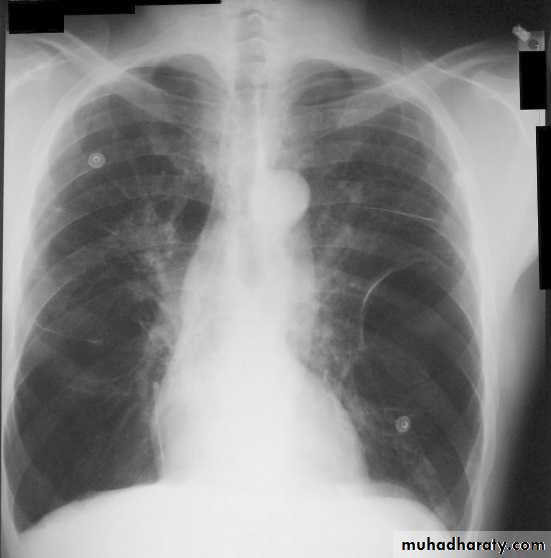

B- Imaging

Chest X-ray: Typical changes of emphysema include paucity of parenchymal markings, hyper-translucency and bulae. Increasing lung volume and flattening of diaphragm suggest hyperinflation.

High resolution CT scan (HRCT) is the definitive test to exclude the diagnosis of emphysema. However, this is only required when planning for surgery